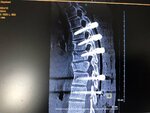

Weißt was ich würd über Unfälle ned so großkotzig reden karma trifft jeden mal und ich dachte mir auch nicht das ich dem Tag mim Hubschrauber ins Spital flieg als heim zu fahren :) ich hoffe nur für dich das du dann soviele Schutzengeln hast wie ich is ned witzig wenn dein Rücken so ausschaut ;)

Anhänge

• 6C4CE2BA-67FD-4F1B-94EA-7C1118E42121.jpeg

6C4CE2BA-67FD-4F1B-94EA-7C1118E42121.jpeg

248,7 KB · Aufrufe: 15